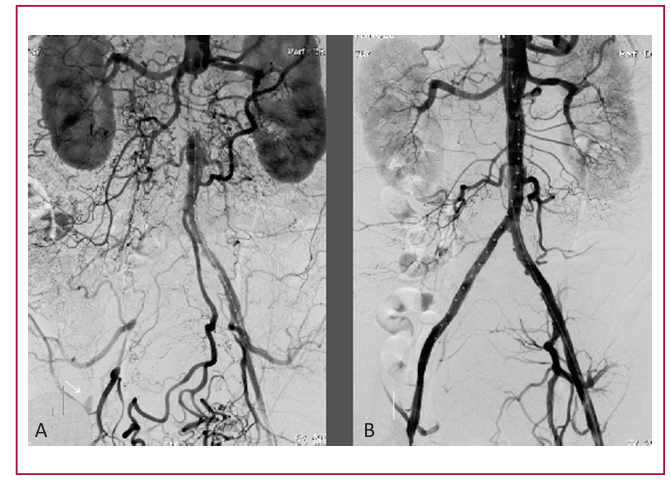

Introducción: La cirugía representa el tratamiento de revascularización tradicional para las lesiones aortoilíacas TASC tipos C y D. No obstante, la morbimortalidad de la cirugía abierta no es despreciable, motivo por el cual en la última década el tratamiento endovascular emerge como una alternativa menos invasiva.

Material y métodos: Se realizó un análisis retrospectivo descriptivo de 32 lesiones ilíacas TASC tipos C y D tratadas de forma endovascular desde enero de 2012 a octubre de 2014. Se evaluaron el éxito técnico, la mortalidad perioperatoria y la permeabilidad.

Resultados: Se consiguió el éxito técnico en las 32 (100%) lesiones tratadas. La media de seguimiento fue de 14 meses, con una permeabilidad primaria del 96,8%. La mortalidad acumulativa durante el seguimiento fue de 2 (6,25%) pacientes.

Conclusiones: En nuestra experiencia, en las lesiones TASC tipos C y D de la región aortoilíaca, el tratamiento endovascular es factible y seguro y presenta una tasa elevada de recanalización. Podría considerarse como una alternativa válida a la cirugía para este tipo de lesiones si estos hallazgos se confirman en estudios de mayores dimensiones, aleatorizados y comparativos de ambas terapéuticas.